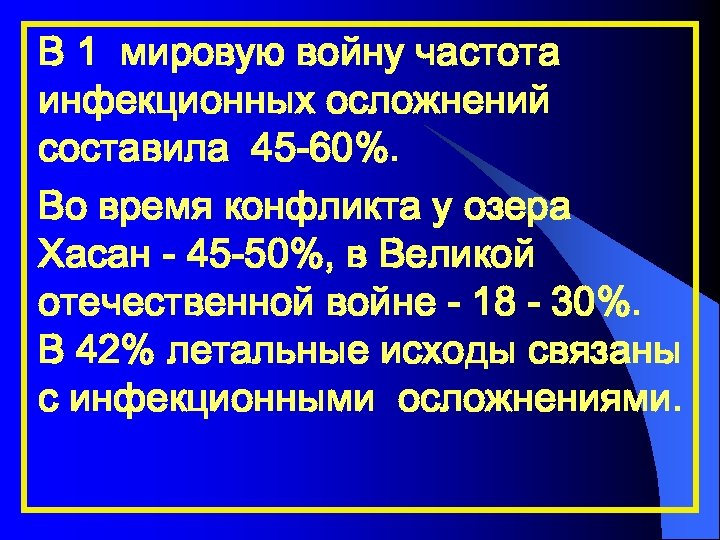

В 1 мировую войну частота инфекционных осложнений составила 45 -60%. Во время конфликта у озера Хасан - 45 -50%, в Великой отечественной войне - 18 - 30%. В 42% летальные исходы связаны с инфекционными осложнениями.

В 1 мировую войну частота инфекционных осложнений составила 45 -60%. Во время конфликта у озера Хасан - 45 -50%, в Великой отечественной войне - 18 - 30%. В 42% летальные исходы связаны с инфекционными осложнениями.